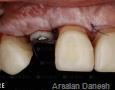

Pictures

Baseline